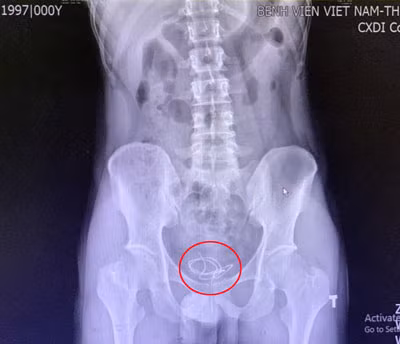

Đoạn dây tai nghe trong bàng quang của người bệnh trên phim chụp X.Quang. Ảnh: BV.

Nam thanh niên 25 tuổi nhập viện với triệu chứng tiểu khó, tiểu buốt, tiểu rắt. Qua thăm khám, dựa trên phim chụp X.quang các bác sĩ phát hiện ra một đoạn dây tai nghe dài chừng 20cm trong bàng quang của nam thanh niên. Người bệnh đã thú nhận rằng chính anh đã tự nhét dị vật vào niệu đạo, không may nó bị đẩy vào quá sâu, dẫn đến mắc kẹt.

Theo Ths. Bs. Nguyễn Như Trung – Khoa Ngoại thận tiết niệu Bệnh viện cho biết: khi tiến hành xử trí cho người bệnh các bác sĩ nhận thấy dị vật là 1 đoạn dây tai nghe điện thoại nằm cuộn lại tại bàng quang của người bệnh. Tiến hành lấy bỏ dị vật ra ngoài nhận thấy niêm mạc bàng quang, niệu đạo đã có hiện tượng viêm đỏ.